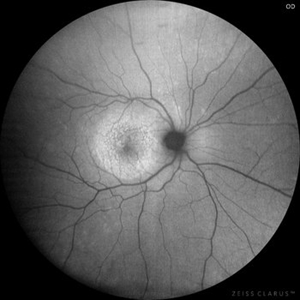

Posterior Placoid Chorioretinitis Posterior Placoid ChorioretinitisMar 9 2025 by Oscar Francisco Miranda, MD A 36-year-old male with bilateral visual loss of 3 months' duration, with no relevant medical history on inquiry. A round-shaped lesion with well-defined borders and a yellowish-white color is observed in the macula of both eyes, accompanied by vitreous cellularity. The macular OCT shows a dentate RPE. The VDRL, FTA-ABS, and HIV tests were positive. Photographer: Oscar Francisco Miranda-Gómez Imaging device: Autofluorescence Zeiss Clarus 700 Condition/keywords: acute posterior placoid chorioretinitis, Autofluorescence, ocular syphilis